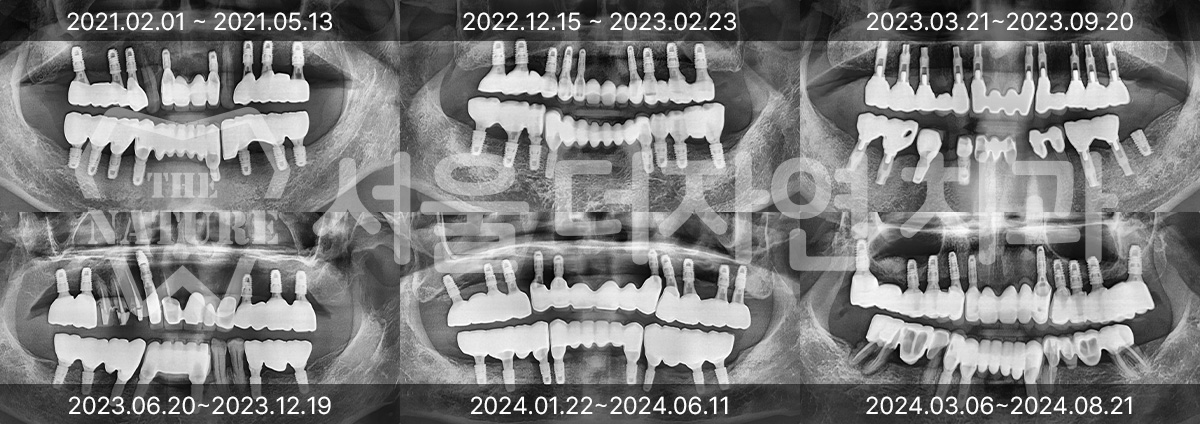

Various Implant Treatment Cases

#Full Mouth Implants

• BEFORE: 2022.12.15

• AFTER: 2023.02.23

#Sinus Lift

• BEFORE: 2021.02.01

• AFTER: 2021.05.13

#Maxillary Bone Grafting

• BEFORE: 2021.11.02

• AFTER: 2022.01.19

Treatment outcomes may vary by patient,

and side effects may occur. These images were taken under the same conditions,

and were published with the patient's consent.